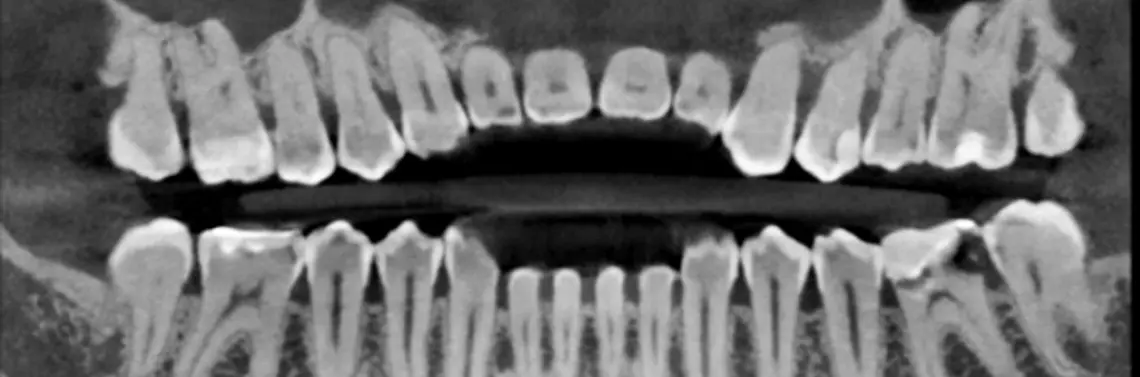

Zdjęcia pantomograficzne są płaskimi obrazami trójwymiarowych obiektów, zatem często nie dostarczają wystarczających informacji na temat wszystkich struktur. Bardzo duży wpływ na ich jakość ma odpowiednie spozycjonowanie pacjenta. Producenci wciąż upraszczają sposoby poprawnego ułożenia głowy pacjenta poprzez zastosowanie specjalnie modelowanych zagryzaków, które mają ustawić zgryz pacjenta w optymalnej pozycji. Niestety, nawet tego typu zabiegi nie chronią w pełni przed rozmyciem istotnych struktur anatomicznych. Jest to często spowodowane niestandardowym ułożeniem łuków zębowych lub odchyleniem pozycji zębów, co w konsekwencji prowadzi do błędnej pozycji obiektów względem osobliwej warstwy ostrości aparatu pantomograficznego (zdj. 3).